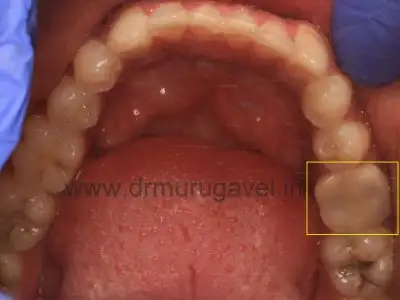

Preoperative view -RCT Treated tooth with crown:

Tender on percussion & grade 1 mobility present in relation to 36.

There was a periapical lesion present in relation to 36 with bone loss .Still there was sufficient cortical bone present to place the dental implants .